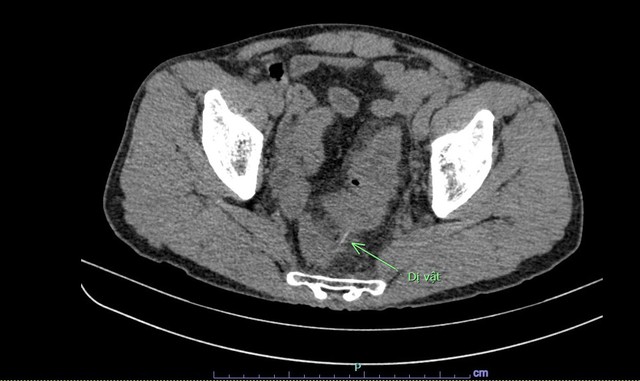

Hình ảnh chụp cắt lớp vi tính cho thấy dị vật đâm thủng đại tràng người bệnh. Ảnh: BVCC

Tại đây, người bệnh đau bụng từng cơn, đau bụng tăng dần. Người bệnh được khám và thực hiện các kỹ thuật chẩn đoán chuyên sâu, nghi ngờ có dị vật đâm thủng đại tràng và được chỉ định phẫu thuật cấp cứu.

Trong quá trình phẫu thuật, bác sĩ kiểm tra thấy đoạn cuối đại tràng xích ma có 1 dị vật dài đâm thủng lòng đại tràng và chui ra ngoài. Lấy dị vật ra thì phát hiện đây là 1 chiếc tăm tre dài 10cm. Sau đó, các bác sĩ đã khâu lỗ thủng đại tràng và làm hậu môn nhân tạo cho người bệnh.